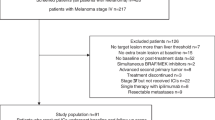

Patients

Sixty-seven patients (44 males, 23 females; mean age 56.9 years) with unresectable, stage IV melanoma undergoing immunotherapy with ICIs were enrolled in this retrospective analysis of a prospectively conducted study. Some of these patients have been analyzed in other publications but with different approaches than in the here presented study [16]. Patients received CTLA-4 inhibitors (ipilimumab), PD-1 inhibitors (pembrolizumab, nivolumab) or a combination of CTLA-4 and PD-1 inhibitors (nivolumab/ipilimumab). Ipilimumab was administered intravenously at a dose of 3 mg/kg every 3 weeks for a total of 4 doses. Pembrolizumab was administered intravenously at a dose of 2 mg/kg every 3 weeks. Nivolumab was administered intravenously at a dose of 3 mg/kg every 2 weeks. The combination ICI therapy was administered as an induction of 4 cycles of nivolumab (1 mg/kg) and ipilimumab (3 mg/kg) every 3 weeks, followed by single-agent nivolumab administration (3 mg/kg) every 2 weeks. The included patients had not received chemotherapy for at least one month prior to the initial PET/CT studies. None of the patients had a history of diabetes. Patients gave written informed consent to participate in the study and to have their medical records released. The study was approved by the Ethical Committee of the University of Heidelberg (S-107/2012) and the Federal Agency for Radiation Protection (Bundesamt für Strahlenschutz, Z 5 – 22,463/2 – 2012–016).

All included patients underwent immunotherapy with at least four cycles of ICIs as described above, without disruption of the treatment due to irAEs or other causes during this period. In specific, they received CTLA-4 inhibitors (ipilimumab, n = 49 patients), PD-1 inhibitors (pembrolizumab, n = 5 patients; nivolumab, n = 2 patients) or a combination of CTLA-4 and PD-1 inhibitors (nivolumab/ipilimumab, n = 11 patients). Baseline mean LDH was 276.0 U/l (median = 234.0 U/l). Median follow up [95% CI] of the patient cohort from start of treatment was 61.5 months [45.3 – 66.7 months]. At the time of data cutoff for the analysis, 38 patients (56.7%) had died. Median OS for all patients was 37.8 months [21.1 – NA] from start of treatment.